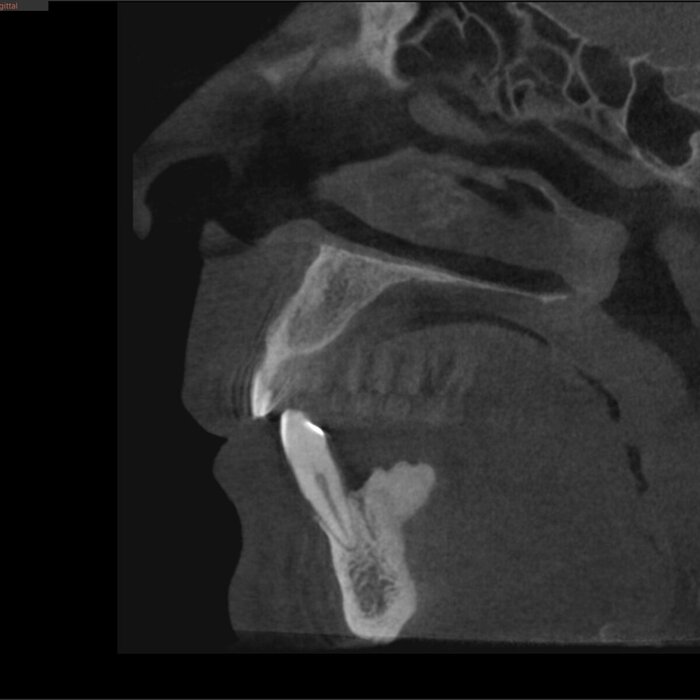

Есть такое. Видела лично и не раз. Кости нет совсем, зубы на снимке КТ "висят в воздухе" или цепляются за жизнь верхушками корней.

Такими зубами не получится жевать, это диагноз "пародонтит тяжёлой степени тяжести", подвижность 3-4 класса (шевеление от акта дыхания). Действительно, уберёшь шинирующую конструкцию из "камня" - зубы посыпятся. Ведь зубные отложения "срастаются" (в кавычки беру это слово) как с корнями, так и с десной.

КЛКТ

Да и смысл добавлять скан - всё видно и понятно. На нижней челюсти 4 зуба, которые никуда не годятся.

Справа - одинокий воин.

Слева - компания друзей навынос.